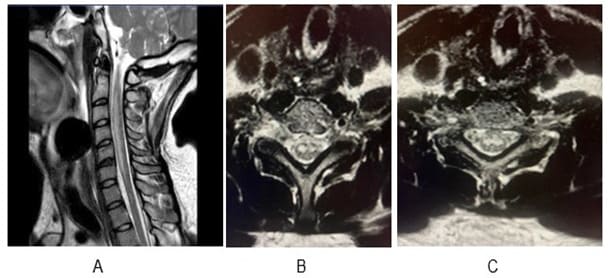

Figure 1A: MRI Cervical spine - Sagittal T2 sequence showing hyperintensity from C2 to C6 in the anterior portion of the spinal cord (ACA territory). Figure-1B and 1C are axial sections showing lesion in the grey matter region (Owl’s eye appearance).

We present the case of a 30-year-old previously healthy man who presented to the ER on a Sunday morning with acute onset difficulty breathing and weakness in his extremities. He spent most of Friday and Saturday with friends. Earlier that morning he had complained of neck pain and tingling in his hands, which prompted his roommate to bring him to the ER. He was able to walk into the ER, soon after he required assistance to stand up. He now reported, “I can’t move” and “I can’t breathe, I want oxygen”. This was followed by agitation, respiratory distress (Oxygen saturation at 31%) requiring intubation and mechanical ventilation. There was no history of trauma, recent surgical procedures, diabetes, hypertension, heart disease, other significant past medical conditions, and no recent travel history. His vital signs showed normothermia soon followed by hypothermia returning to normothermia (98-degree F; dropping to 94-degree F and 98-degree F over 3 hours), BP 160/98 (then 116/61; followed by 56 mm Hg systolic that improved with fluid boluses. Heart rate was 66/min and later 36/min improving to 80s (36-137 range); EKG showed alternating sinus rhythm and atrial fibrillation with rapid ventricular rate. On day 2 patient failed extubation due to very low tidal volume (80 ml). Chest CT did not show any pathology to explain respiratory failure. His exam revealed quadriplegia and this led to a neurology consultation. Neurological examination showed intact consciousness; he responded to loud verbal and physical stimulation with nods or head shaking. Eye movements initially showed dysconjugate gaze (this resolved in 24 hours), patient exhibited flaccid (0/5) quadriplegia, areflexia and down-going plantar response. He however managed to dislodge the endotracheal tube (ETT) with his tongue movements multiple times. He had normal sensation in his face; below his neck, he had decreased sensation to temperature and pain, but intact light touch and proprioception. Head CT did not show any acute abnormalities. Other investigations on admission revealed normal CBC, CMP; urine drug screen was positive for THC and negative for stimulants, blood EtOH level was < 3. Additional tests included CSF analysis with cell count of 7, normal protein and glucose. CSF culture later came back negative, and he had a normal sed rate (ESR). Brain MRI revealed numerous subcentimeter bilateral cerebellar, posterior temporal and occipital embolic infarcts (Figure 2 A- 2E and Figure 3). Magnetic Resonance Imaging of the cervical spine showed T2 hyperintensity in the territory of the anterior spinal artery extending from C2 to C6 (Figure 1). MRA of the head and neck were normal (Figure 4A and 4B). Transthoracic Echocardiography showed normal ejection fraction, no intracardiac structural abnormalities and no right to left shunt. Transesophageal echocardiography did not reveal any abnormalities in the proximal aorta. CT angiography of head and neck done few days later was normal as well indicating no occlusions or dissections (Figure 5A-5E). He received 1-gram intravenous solumedrol daily for five days based on initial cervical MRI findings in addition to aspirin started after MRI showed acute infarcts. His CSF also showed 14 oligo clonal bands (unclear significance likely secondary to acute ischemia). Hospital course – On day 3 he went into neurogenic shock and multiple episodes of vasovagal bradycardia (HR in the 40s) and demonstrated hemodynamic instability when he was being moved by nursing staff. His exam now showed intact cognition and normal cranial nerve examination. He developed ileus and had frequent episodes of bradycardia (Figure 6), fluctuating blood pressure all part of autonomic dysfunction causing the nurses to panic. He required transvenous pacemaker which was soon replaced with permanent pacemaker. After four weeks his tidal volume improved from 80 ml to 240 ml., he started to regain significant strength in his lower extremities to the point where he was able to stand up and walk up to 25 feet when his vital signs permitted. His upper extremities remained flaccid, areflexic except for his ability to close his hands to gently squeeze a soft ball. Repeat labs including spinal fluid showed similar findings including 14-oligoclonal bands, normal cell count, protein, and glucose. West Nile virus IgM, HTLV-1, HIV, HSV and CSF VDRL testing were all-negative. After eight weeks, his autonomic instability continued to improve and so did his participation in physical therapy sessions. He could now ambulate up to 100 feet using a special walker; however, he remained flaccid in his upper extremities and continued to need intermittent daily ventilator support due to tidal volume at ~300ml. Repeat MRI of his brain and spinal cord was placed on hold due to his pacemaker that requires many weeks for lead maturation.